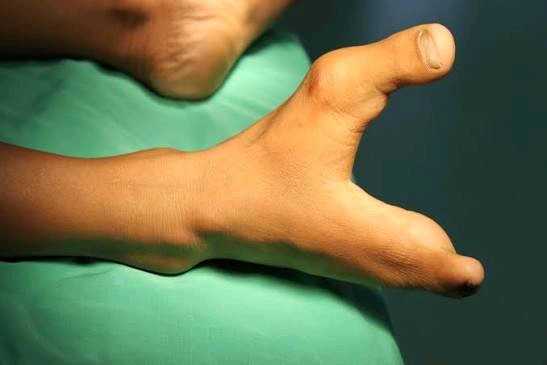

NSFW

Нажмите, чтобы открыть